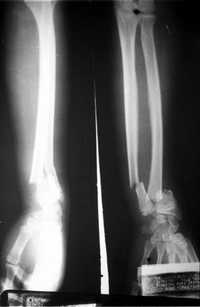

Utilizando novedosos métodos biotecnológicos de esterilización y preservación, una empresa de México procesa tejido músculo esquelético humano para obtener implantes estériles de hueso y tendón, los cuales pueden utilizarse en el tratamiento de diversas lesiones óseas o rupturas de ligamentos.

Los implantes de hueso Biograft pueden ser utilizados para atender lesiones de columna vertebral, cadera, rodilla, quistes óseos, etcétera. En tanto, los implantes de tendón permiten sustituir, por ejemplo, el ligamento cruzado anterior de la rodilla.

El director de Biograft subrayó que el uso de los implantes de tejido músculo-esquelético tiene múltiples ventajas sobre otras opciones de tratamiento -como son los autoinjertos o el uso de placas o prótesis metálicas-, entre ellas destacan: una recuperación más rápida y menos dolorosa para el paciente, además, no hay riesgos de infección y tampoco rechazo al implante.